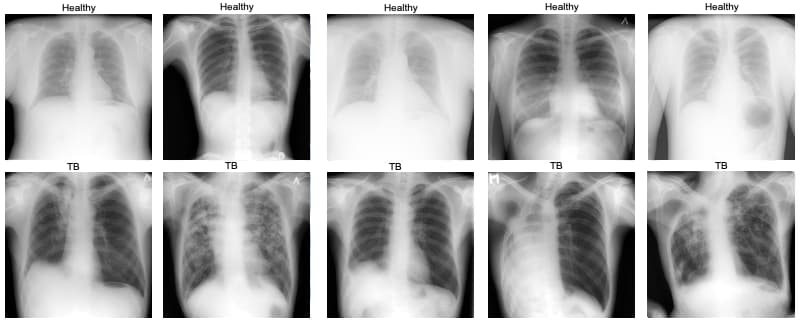

Tuberculosis (TB) is a leading infectious disease affecting the lungs. Clinicians often use chest X-rays to support diagnosis, but reviewing many images manually is time-consuming and challenging. In this competition, you’ll build a simple classifier to distinguish between healthy lungs and lungs affected by TB, focusing on your process, decisions, and learnings rather than perfection.